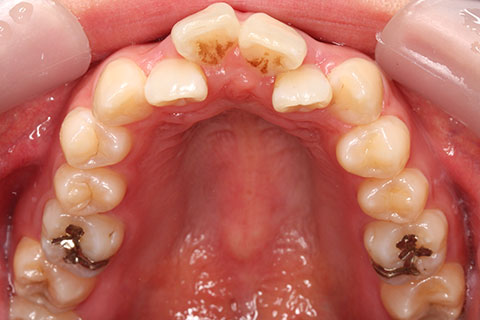

ハーフリンガル矯正4:上の歯のみ舌側矯正で治療(矯正期間24ヶ月)

- 年齢・性別

- 23歳女性

- 治療期間

- 2年0ヶ月

- 抜歯

- 上下4番抜歯

- 治療費

- 110万円

- 備考

- マルチブラケットを用いた矯正治療

- 治療内容

- 施術の副作用(リスク)

- 表側矯正と比較して、前歯のラビッティング(舌側傾斜)を起こしやすい。